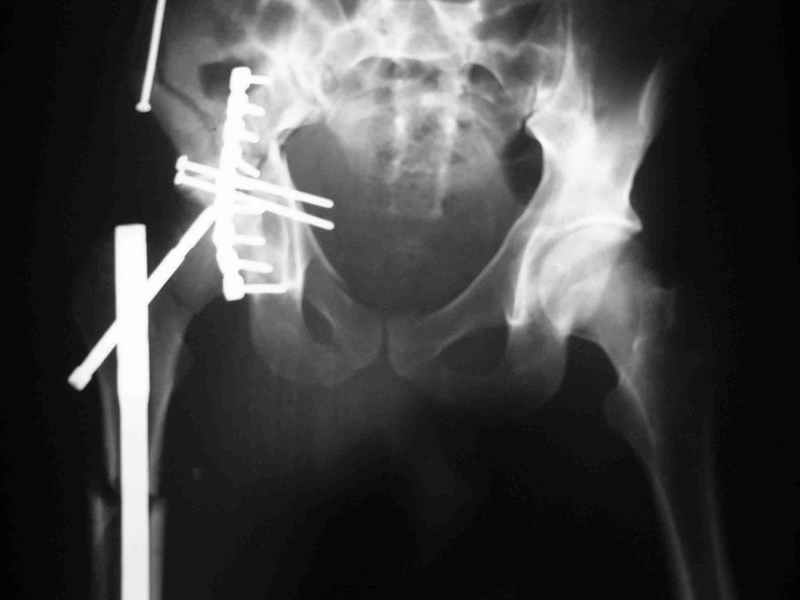

Не дождавшись советов, в понедельник прооперировал больного, заняло времени..., но все сделал в один этап: сначала фиксировал ипсилатеральный перелом бедра и шейки реконструктивным гвоздем Smith&Nephews, потом из расширенного илеофеморального доступа фиксировал перелом крыла подвздошной кости тягловым винтом, нейтрализующей пластиной заднюю колонну, и тягловыми винтами 3,5 мм переднюю колонну.

Несмотря на расширенный доступ, особой кровопотери не было, перелил только одну дозу эр.массы и на утро Нв- 10.5 и как ни странно больной не жалуется на сильные боли и стопа не *висит*, хотя при интраоперационной ревизии седалищного нерва обширная гематома в периневральной оболочке.

К сожалению, набора для ретроградного или антеградного реконструктивного штифтования в операционной нет, поэтому доставка заняла н-ное время. Вопрос, который возник у меня- по поводу оптимальной тактики хирургии: вся фиксация в один этап из расширенного доступа или последовательно сначала бедро и позже реконструкция впадины, комбинированный доступ к впадине отдельно к передней и задней колоннам или из расширенного илеофеморального одного доступа. Все-таки решил остановиться на одноэтапном подходе и спустя 5 дней (как раз и наборы привезли) из расширенного илеофеморального доступа сначала фиксировал реконструктивным штифтом Smith&Nephews бедро и

шейку (благо перелом шейки 2 типа -относительно стабильный) затем фрагмент крыла подвздошной кости Lag screw, далее пластина на заднюю колонну и винты в переднюю колонну.(с размерами и направлением винтов ошибка вышла:-((, но интраоперационно у меня была полная уверенность , что винты *ушли* в лонную кость).

Еще раз спасибо за комментарии и готовность помочь с имплантами. Постоп картинки в приложении,

Высылаю пример еще одного случая, остеосинтез пластиной из подвздошного доступа.